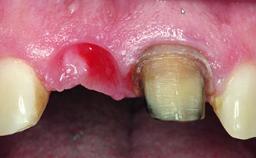

A 49-year-old female patient was referred for implant therapy to replace the upper right central incisor (tooth 11). The tooth had been assessed by an endodontist who diagnosed a vertical fracture of the root. The tooth had a hopeless prognosis and needed to be extracted. The patient was healthy and was not taking any medications. She was allergic to penicillin. The patient had high esthetic demands but her expectations were realistic. The extraoral examination revealed no facial asymmetries. The right temporomandibular joint demonstrated an opening click but was otherwise asymptomatic. The lip line was high with a significant gingival display.

Soft Tissue Anatomy Intact Defective

Bone Volume Horizontally and vertically sufficient Horizontally deficient Deficient vertically or deficient vertically AND horizontally